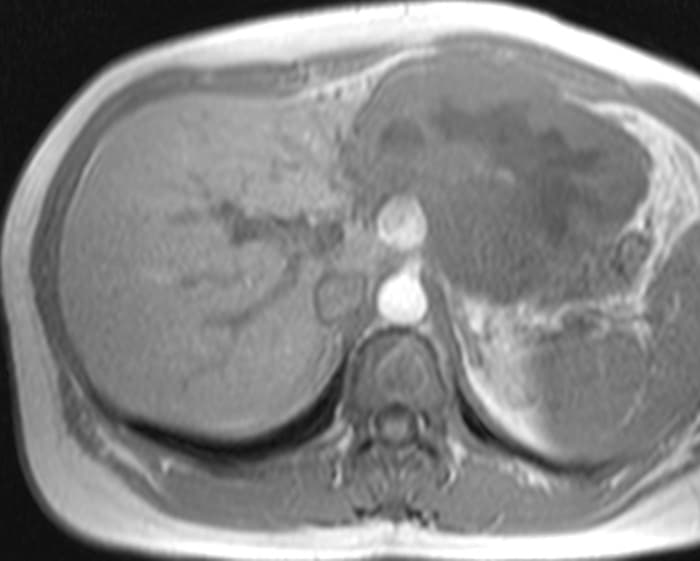

U máu gan

» Thông tin: Nữ giới – 47 tuổi.

» Lâm sàng: Đau thượng vị.